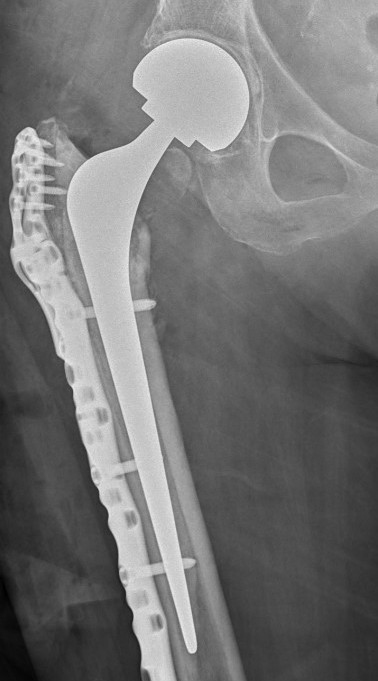

C. Hemiarthroplasty / THA

Infected nonunion